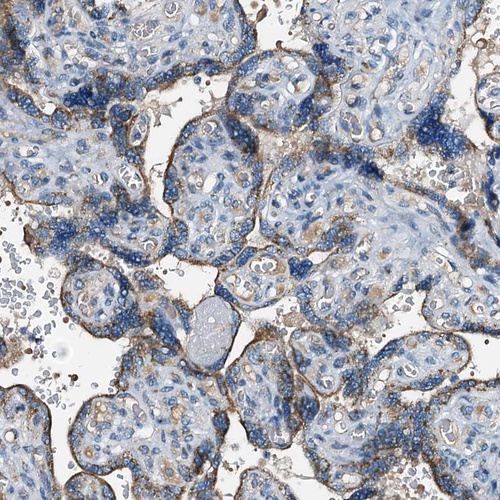

Immunohistochemical staining of human testis shows strong granular cytoplasmic positivity in Leydig cells.